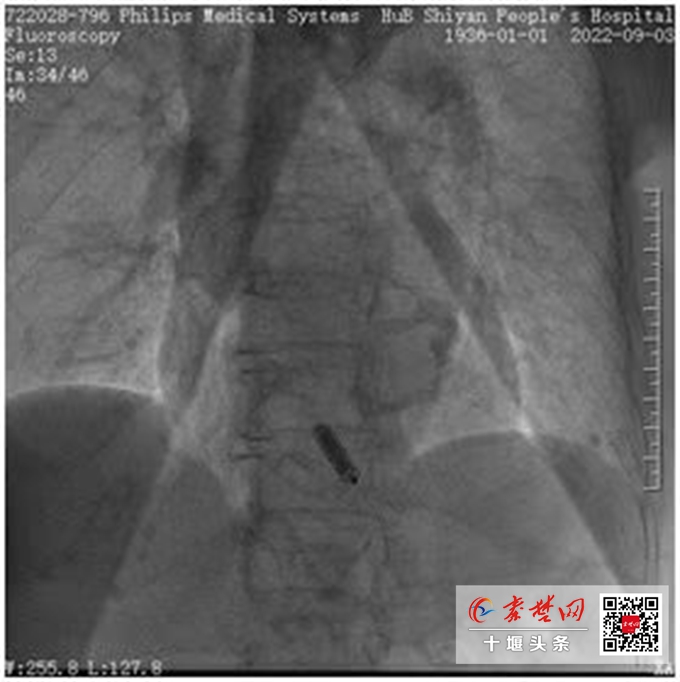

无导线起搏器从外观看只有胶囊大小,功能却与传统的起搏器无异(造影效果)

结合高奶奶的情况,张友恩博士团队提出采用国外最先进的无导线起搏器技术进行微创手术治疗。“Micra无导线起搏器,又称胶囊起搏器,因为从外观看只有胶囊大小,功能却与传统的起搏器无异。手术时,无导线起搏器不需植入电极导线,也无需在胸前区做切口,只需在患者腿部穿刺处打点麻药,将胶囊大小的起搏器经静脉植入右心室心尖部即可。手术无切口,无疤痕,术后感觉不到起搏器的存在,几乎避免了常规起搏器面临的手术创伤、出血、感染等风险。而且兼容1.5 T/3.0 T全身核磁共振扫描检查,同时其超低功耗电路设计可以支持平均大约12年电池寿命。”张友恩介绍。